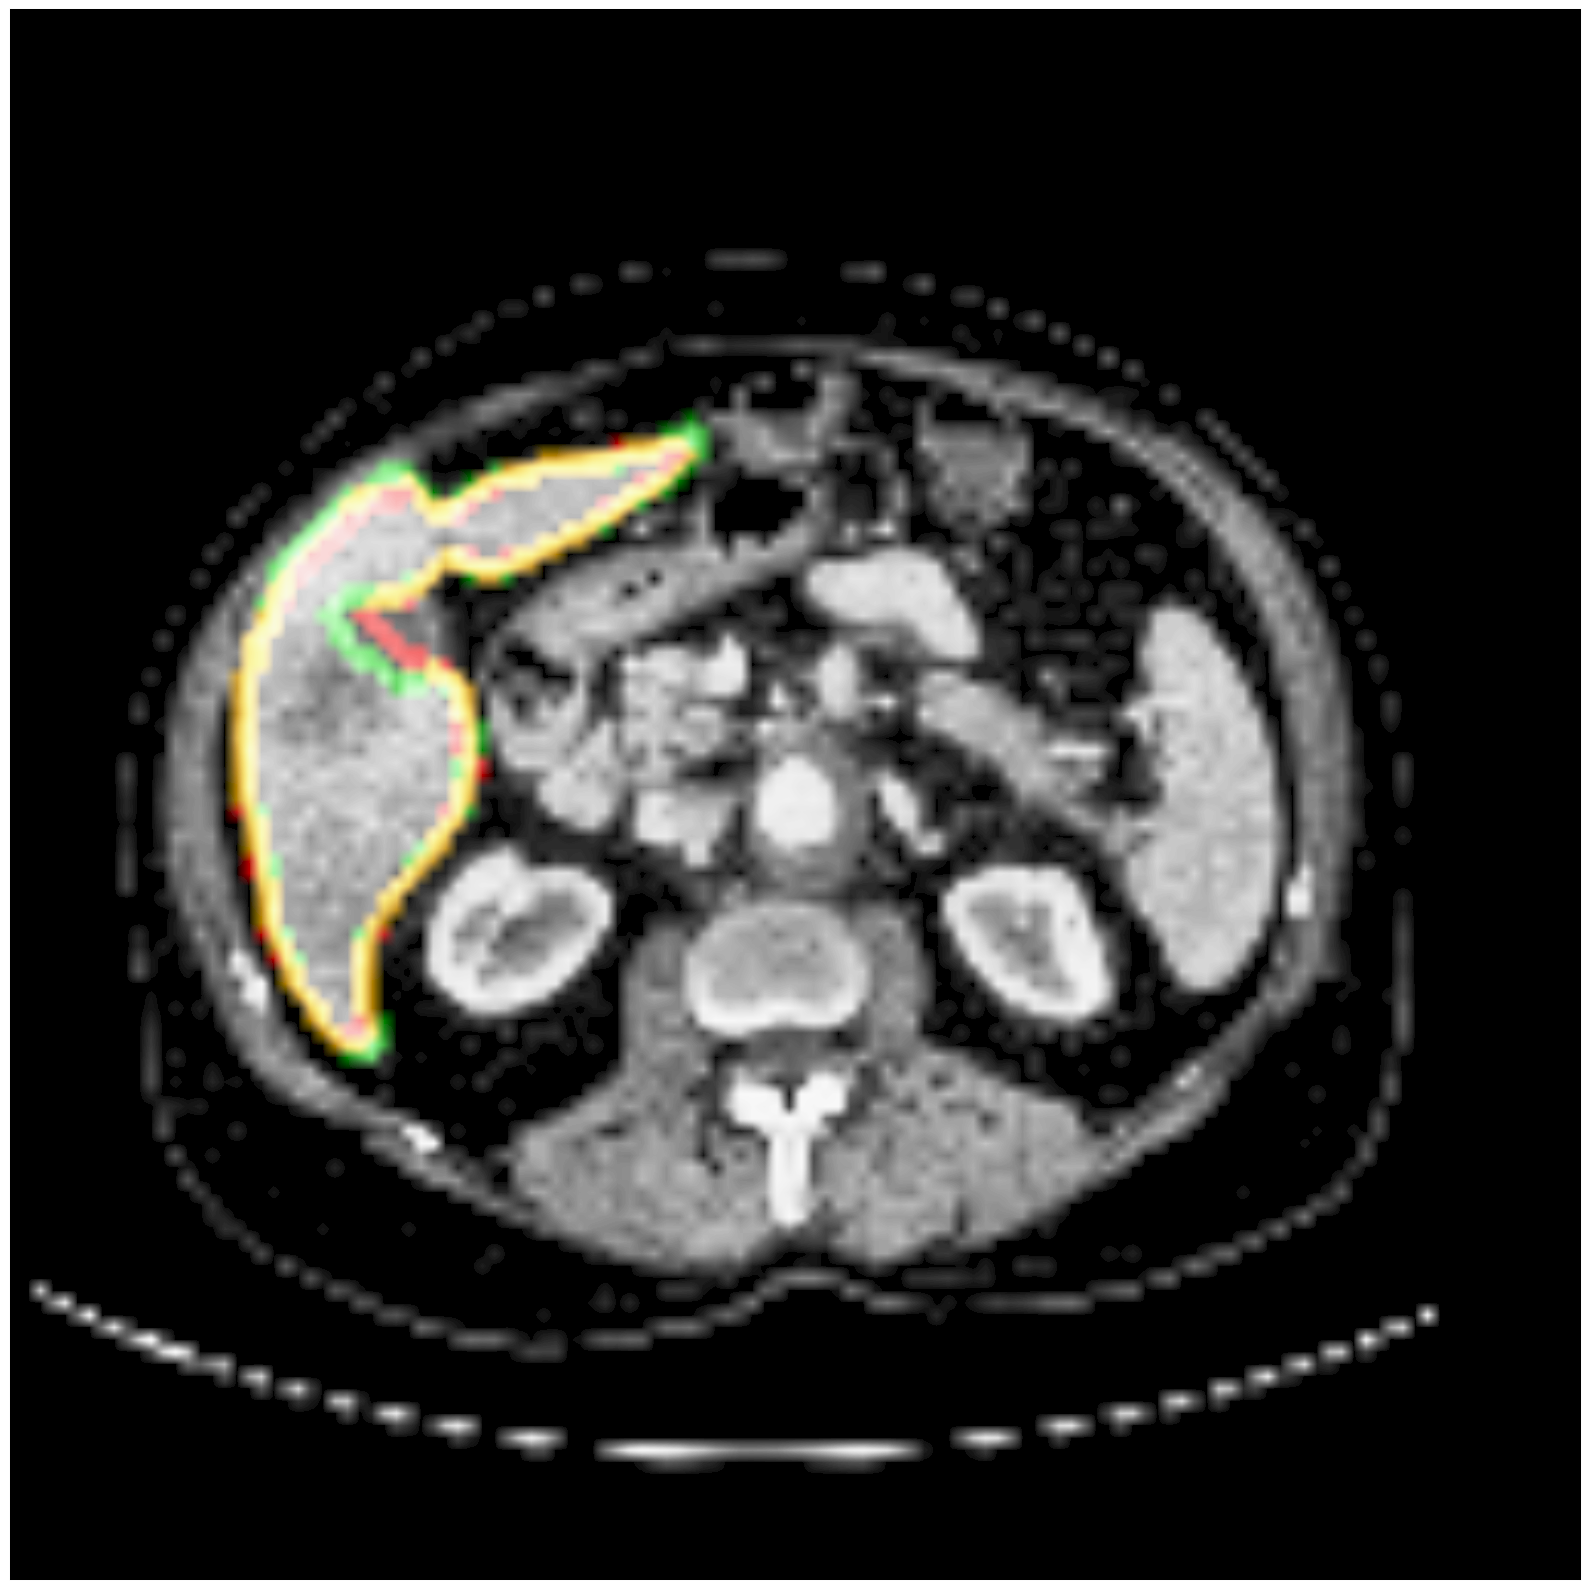

Some segmentation results at different vertebrae (top) and liver (bottom) areas are depicted in Fig. 2. The red contour corresponds to the outline of the prediction, green to the ground-truth and yellow to the overlap of the outlines.